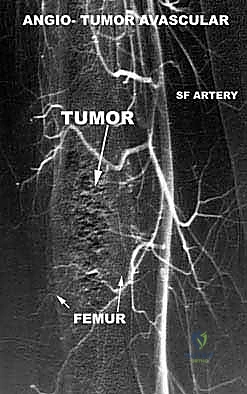

تحديد مراحل الورم (Staging): نظام Enneking

تحديد مرحلة الورم هو الخطوة الأهم قبل أي تدخل جراحي. يعتمد الدكتور هطيف على نظام (Enneking) لتحديد مراحل أورام العظام، والذي يعتمد على ثلاثة عوامل:

1. درجة الورم (Grade - G): بناءً على الفحص النسيجي (G1 منخفض الدرجة، G2 عالي الدرجة).

2. الموقع (Site - T): هل الورم داخل الحيز العظمي (Intracompartmental - T1) أم اخترق القشرة وخرج للحيز الخارجي (Extracompartmental - T2)؟

3. الانتشار (Metastasis - M): هل انتقل الورم لأعضاء أخرى (M0 لا يوجد، M1 يوجد انتشار)؟

بناءً على هذا التقييم الدقيق، يتم وضع خطة جراحية متكاملة لضمان استئصال الورم بالكامل دون ترك أي خلايا سرطانية.

مبادئ الاستئصال الجراحي: الهوامش الجراحية (Surgical Margins)

الهدف الأول في جراحة الساركوما ليس فقط إزالة الكتلة المرئية، بل استئصالها مع طبقة من الأنسجة السليمة المحيطة بها لضمان عدم ترك أي خلايا مجهرية. تُصنف الهوامش الجراحية إلى:

- الاستئصال الواسع (Wide Resection): وهو المعيار الذهبي. يتم استئصال الورم مع طبقة من الأنسجة السليمة المحيطة به (العضلات، العظام). هذا ما يبرع فيه الدكتور هطيف لضمان الشفاء التام.

* العلاج الكيميائي قبل الجراحة (Neoadjuvant Chemotherapy): يُعطى لتصغير حجم الورم، مما يسهل عملية الحفاظ على الطرف، ويقتل الخلايا السرطانية الدقيقة المنتشرة في الدم.

يتم تقييم مدى استجابة الورم للعلاج الكيميائي (Tumor Necrosis Rate) بعد الاستئصال، وهو مؤشر قوي لفرص الشفاء التام.